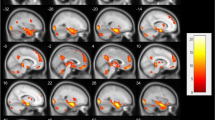

Network analysis

The network for patients with BD-I showed a reduced interrelationship in the frontal–insular–occipital regions (superior frontal gyrus, middle frontal gyrus, inferior frontal gyrus, orbitofrontal cortex, insula, fusiform gyrus) relative to those with BD-II and HC, as well as between FER-sadness and FER-neutral (see Fig. 4). In patients with BD-I, FER-sadness, and FER-neutral were not associated with frontal–insular–occipital regions, and the strength of the FER-sadness–amygdala edge was greater compared to the other groups (HC had a negative sign in this edge). NCT confirmed a significant difference in the network structure invariance between patients with BD-I and HC (p < 0.001) as well as between patients with BD-II and HC (p < 0.001). In contrast, no differences were observed between the BD subtypes (p = 0.85). We did not find any difference in terms of global strength invariance among groups (all p’s > 0.1). Finally, the edge invariance test, which compares the edge (connection) strength [77], confirmed a stronger positive relationship between FER-sadness and amygdala GMV in patients with BD-I relative to HC (p = 0.005) but not between HC and those with BD-II or between BD subtypes (all p’s > 0.1). We did not find any significant differences in centrality measures between diagnoses (see Table S.2 for descriptive statistics on these measures).

Network plot of the relationship between facial emotion recognition and brain morphometry of the regions implicated in facial emotion recognition (FER) for each diagnostic group. The thickness of the edge represents the strength of the correlation, and its color represents the sign of the correlation. The red lines indicate positive associations; blue lines indicate negative associations. The nodes are grouped by color: green for emotion recognition: Sadness FER-sadness score, Neutral FER-neutral score; purple for limbic cortex morphometry: Insula, Amy amygdala, Hippo hippocampus, ACC anterior cingulate cortex; orange for fronto-insulo-temporal cortex morphometry: FUS fusiform gyrus, SFG superior frontal gyrus, MFG medial frontal gyrus, IFG inferior frontal gyrus. The FER performance was calculated as the ratio between the % accuracy and the reaction time. Brain morphometry was measured as the average gray matter volume extracted from bilateral regions of interest using voxel-based morphometry. BD-I bipolar disorder type I, BD-II bipolar disorder type II, HC healthy controls

In this study, three main findings emerged. First, euthymic patients with BD-I had the poorest performance in recognizing facial emotion expressions, particularly sadness. Second, in those with BD-I, FER performance, specifically for sadness, was correlated with illness duration and GAF scores. Additionally, FER for sadness in patients with BD-I was negatively associated with the number of previous manic episodes. Third, the overall structure of the network of patients with BD-I and patients with BD-II was altered, with a reduced GMV interrelationship in the frontal–insular–occipital regions in those with BD-I. Furthermore, the edge strength between sadness-related FER performance and amygdala GMV was stronger in patients with BD-I compared to the other groups, according to the edge invariance test. Lastly, FER performance during the presentation of sadness was poorer compared to neutral in patients with BD-I and HC but not in those with BD-II.

Furthermore, we found a stronger positive relationship between FER-sadness and amygdala GMV in patients with BD-I relative to HC (p = 0.005), as emerged using the edge invariance test. Notably, FER-sadness in patients with BD-I was not associated with GMV in the fronto-insular areas (see Fig. 4). The ability to recognize sadness in patients with BD-I appears to be more dependent on amygdala morphometry rather than on frontal–insular–occipital areas, thus confirming that amygdala alterations may be a crucial feature of the disorder [96, 97]. In BD-I, an altered cortico-limbic circuit could underlie altered emotional processing [98, 99]. In keeping with this, previous functional neuroimaging studies reported a reduction of the connectivity between the amygdala and the ventral-PFC [100], the dorsolateral-PFC [101], and the perigenual anterior cingulate cortex [102, 103]. Overall, our findings support a consensus model in which BD-I results from abnormalities in the structure and function of key emotional control networks leading to decreased connectivity between the ventral-PFC and limbic brain regions, especially the amygdala [104].